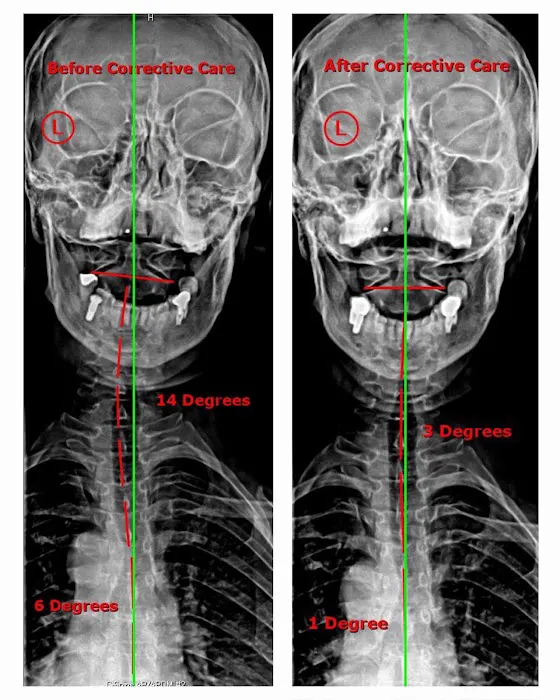

Align Chiropractic offers a comprehensive suite of services designed to address a variety of health issues, with a strong emphasis on corrective and long-term care. The practice uses a combination of time-tested chiropractic techniques and modern technology to provide effective treatment. Before beginning any treatment, the team takes the time to conduct a thorough examination, which often includes x-rays, to get a clear picture of a patient's unique needs and the root cause of their discomfort. This detailed diagnostic process allows them to create a truly personalized treatment plan. The services are not just for those in pain; they are also beneficial for individuals seeking to improve their posture, athletic performance, or general wellness. The focus on educating patients and providing them with tools for at-home care ensures that the benefits of the treatment extend far beyond the office visits.

May 19, 2025 · Christine OI went to Align after going to a chiropractor, massage therapist, physical therapist, and doing different stretches and yoga. I could not put my socks on in the morning. That was the litmus test. After Xrays there was misalignment from the neck down to the lower back. More significantly I had three bulged discs due to bad posture, fractured coccyx, sitting down for long periods. 6 months later after intense home trainings and multiple sessions a week, I could move freely. 2 years later I can go back to squatting and deadlifting my weight and more. To this day I still do the home exercises with the equipment that was provided.